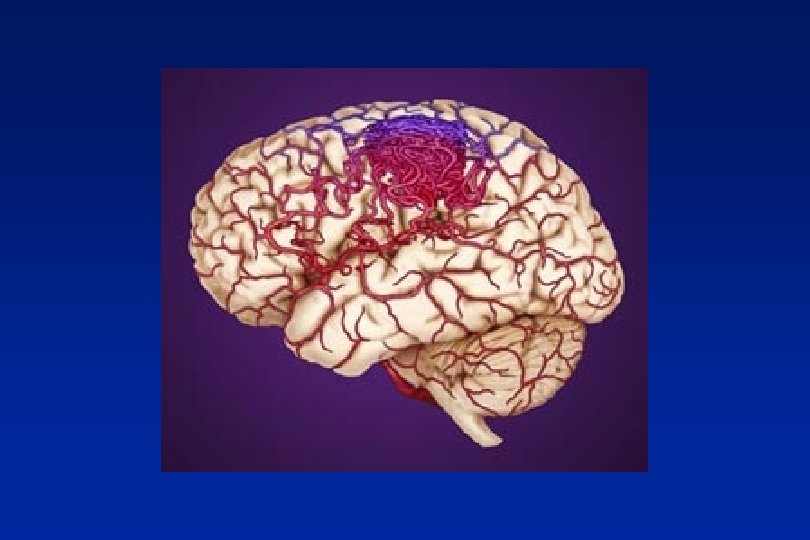

1. 2. 3. 4. 5. Migraine generator – gastric and cervical implications Central and peripheral sensitisation Activation trigeminal nerve Peripheral inflammation Cortical depolarisation and vasoconstriction Classifying headache 2

Implications for gastric stasis and neck pain